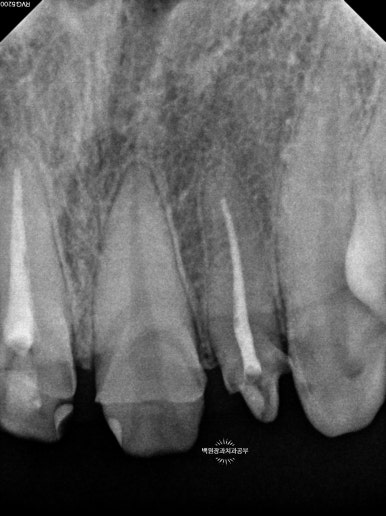

얼마나 충치가 진행되었는지 눈으로만 확인하지 않습니다.

치근단 사진을 촬영하여 보다 자세히 살펴볼 수 있었습니다.

눈으로 보는 것과 같은 위치입니다만, 엑스레이로 보았을 때 현재 위치하는 충치가 치아 내부의 신경관과 얼마나 가까이 위치하는지를 확인할 수 있었습니다.

이에 가장 충치가 심했던 측절치는 신경치료를 할 가능성이 아주 높으며 기둥을 설치해야 한다는 정보를 얻을 수 있었습니다.